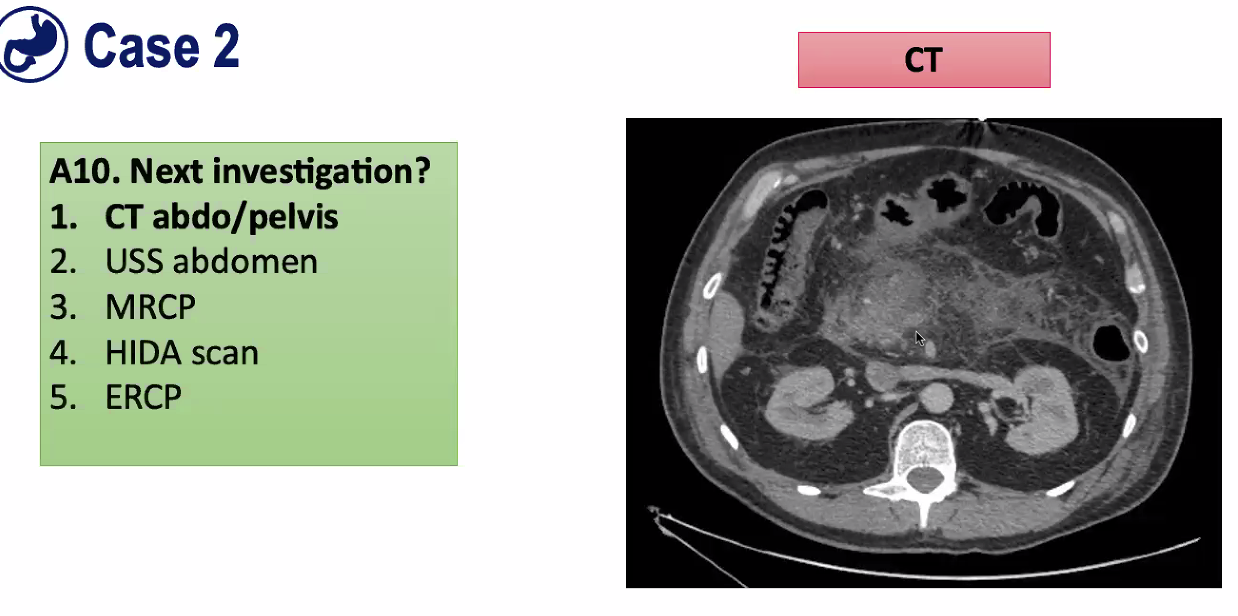

Something has obviously changed, so what investigation would you do now?

=CT abdo/pelvis, as a week down line so now might get complications of pancreatitis. Can see pancreatic juice muching at fat and causing inflammation so pancreas looks fuzzy. Nasty inflammatory mess, nothing you can drain. Just done a CT scan to exclude another problem.